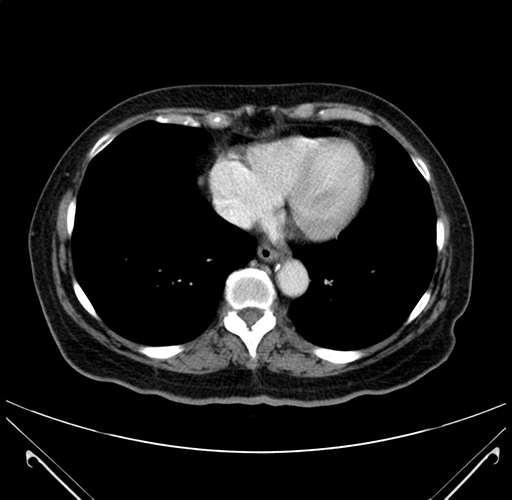

Pre-Chemo: Axial Venous